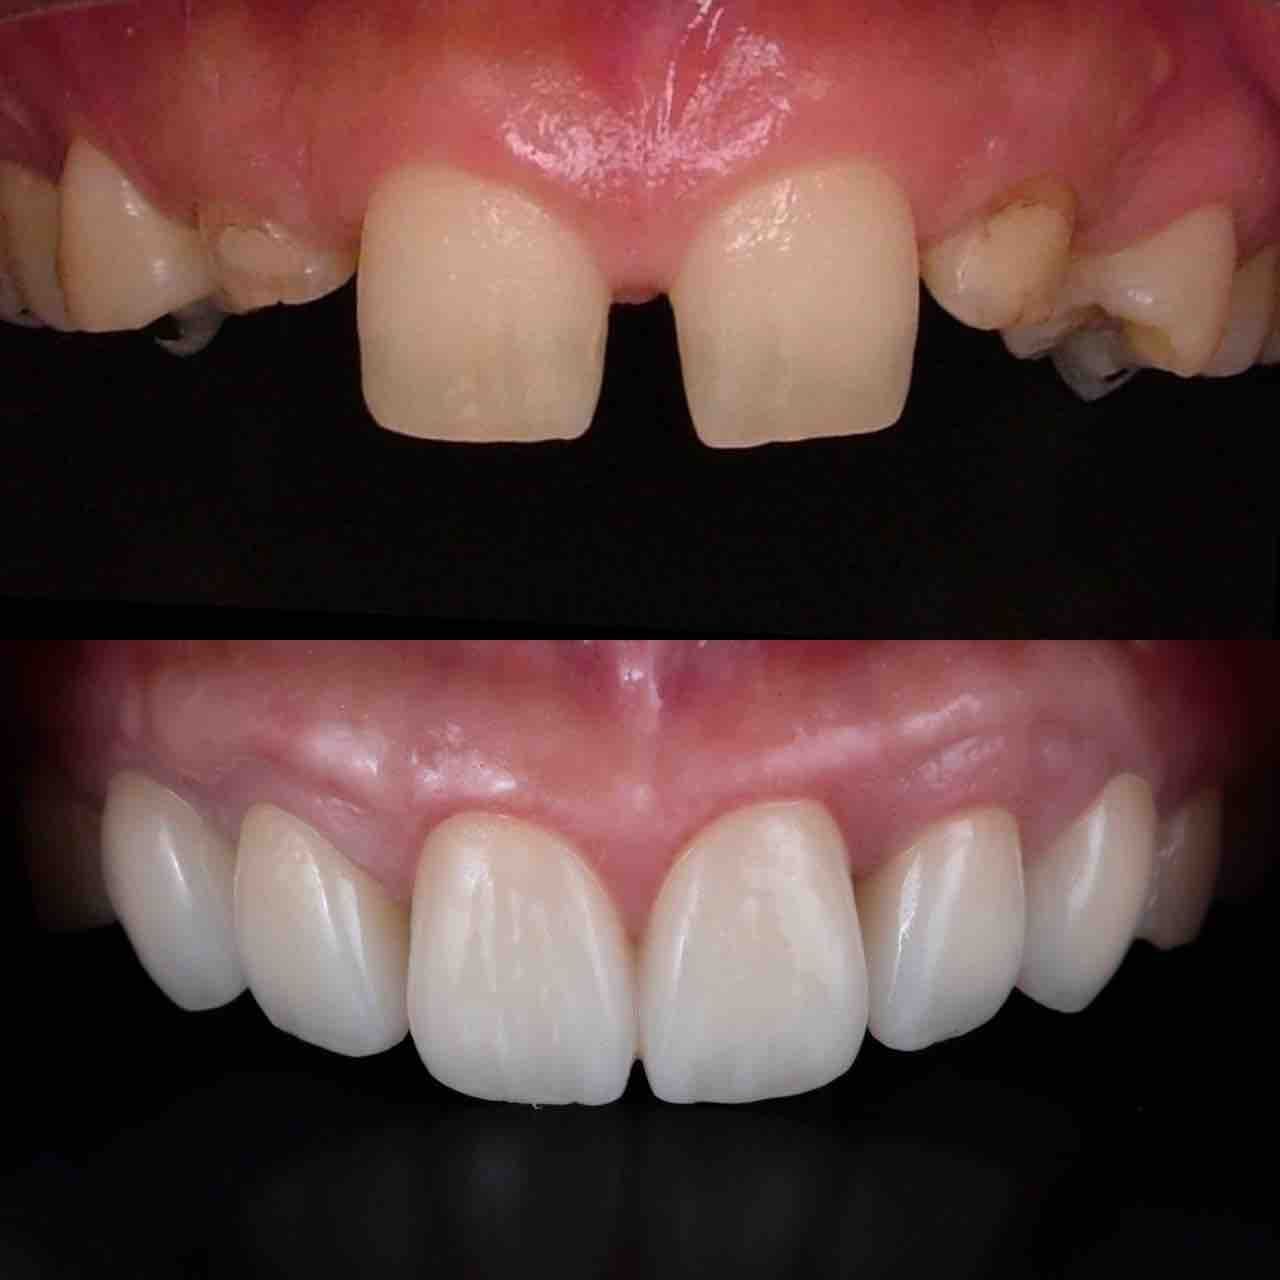

¥¤¥ó¥¹¥¿¥°¥é¥à¤ËºÜ¤»¤Æ¤¤¤ëÅö±¡¤Î¾ÉÎã¤Ç¤¹